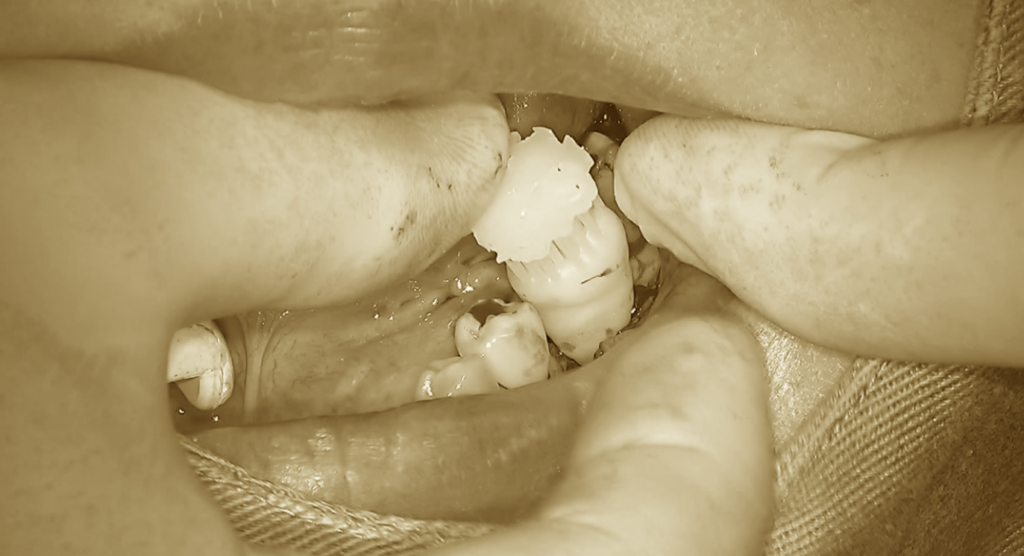

移植床の形成がおおよそのサイズまで整った段階で、

歯牙レプリカを用いて適合の確認を行います。

この時点では、まだ完全にはフィットしていないため、

再度細かい調整を加えていきます。

まずは深さが適切かどうかの確認を行います。

予定している位置までしっかり確保できているかを見極め、

問題がないことを確認したうえで、

今度は横幅の調整へと移ります。

再度、歯牙レプリカを試適します。

今度は無理なくスムーズに収まり、

適切な位置で安定することが確認できました。

これで移植床の準備は完了です。